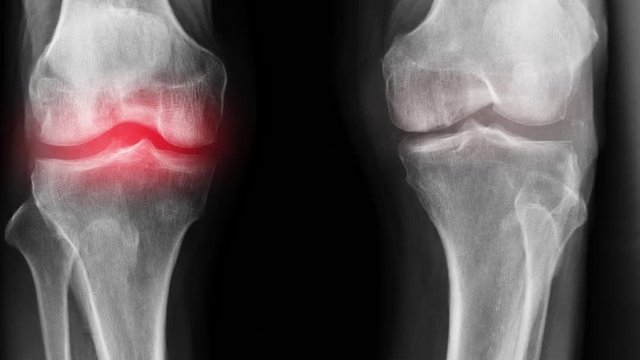

La préparation a été créée à partir de la formule de Sarah Sibanda. Il favorise le processus de guérison du tissu cartilagineux au niveau cellulaire, arrête le processus de détérioration articulaires et élimine la source de l'infection. Le médicament élimine les anomalies dans le liquide synovial et restaure la fonction des articulations, il augmente également la flexibilité des articulations en raison de sa propriété anti-mortification améliorée. On a nommé le produit - Marukaya Сream.

Franz Geisler : Merci à vous. Je voudrais conseiller à tous les lecteurs d'essayer de résoudre leurs problèmes articulaires, car ils sont à l'origine de maladies graves telles que l'arthrite, l'arthrose, la bursite et d'autres maladies dangereuses.